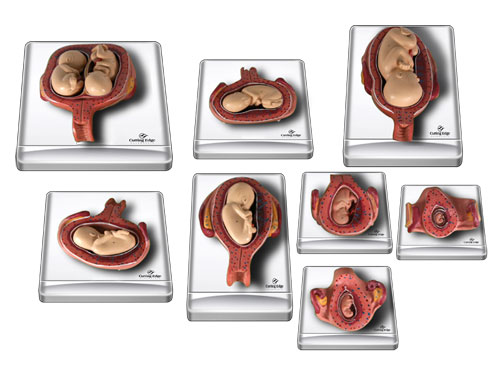

На малюнку 1 Ви бачите зародок людини

Мал. 1. Зародок людини

Які ж етапи проходить зародок, перш ніж сформується повноцінний плід?

У людини зародок формується перші 8 тижнів вагітності. У цей час із заплідненої яйцеклітини формується тіло з основними людськими ознаками.

Перший період розвитку зародка починається відразу ж після запліднення яйцеклітини, в якій розміщені 2 ядра з 46 хромосомами (23-ма від батька і стільки ж від матері). Потім ядра зливаються, утворюючи одноядерний зародок. Після цього ембріон прямує до матки по фаллопієвих трубах. Матка при цьому також готуватися прийняти зародок - товщають стінки, збільшується кількість кровоносних судин, утворюється плацента, в якій і буде розвиватися плід до самого народження.

На четвертому тижні починають формуватися всі органи і тканини, необхідні для життя. На 6-ій - починаються формуватися ручки, а на другому місяці - ніжки. Далі формування зародка не відбувається - до кінця вагітності плід лише зростає і розвивається.

Подивіться на малюнок 3. На ньому відображені положення зародків при різних типах вагітності.

Мал. 3. Положення зародка